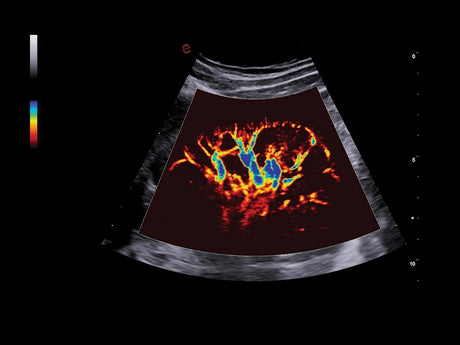

La qualité d’image est au cœur de la philosophie Esaote. Grâce à ses sondes de dernière génération et à son traitement du signal avancé, la marque permet une visualisation fine des structures anatomiques, même les plus profondes. Leurs échographes intègrent des écrans tactiles haute résolution, une interface claire et une connectivité complète, favorisant un flux de travail rapide et efficace.

Les échographes Esaote offrent une restitution d’image d’une grande précision, permettant un diagnostic fiable dans toutes les spécialités. Le traitement numérique optimise le contraste et la netteté, réduisant les artefacts et améliorant la détection des tissus pathologiques. Ces performances sont particulièrement appréciées en gynécologie, où la lisibilité des structures pelviennes ou obstétricales est déterminante.